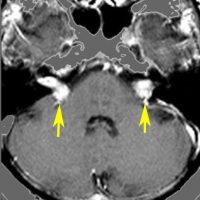

赤の矢印が,両側の聴神経腫瘍です。黄色の矢印は, 多発性の髄膜腫です。蝶形骨縁髄膜腫,穹隆部髄膜腫,大脳鎌髄膜腫,大脳鎌テント接合部髄膜腫などいっぱいあります。これらは基本的に経過観察しますが,とても目立って大きくなるものがあれば摘出します。摘出には注意が必要で,近い将来また手術になるかもしれないので,次回の手術もできるように工夫して開頭手術しなければなりません。でないと,次の手術での合併症が増えます。また一回の開頭で近傍の硬膜や腫瘍を可能な限り摘出してしまうことも大切です。でないと,限りなく手術を繰り返すことになります。